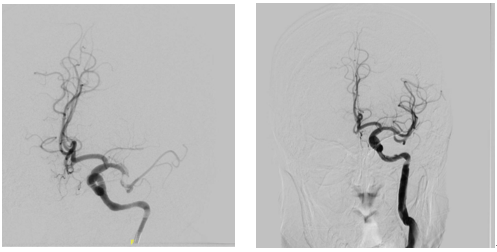

一名 40 岁男性因突发言语不清、右侧肢体无力送至我院急诊。影像检查提示左侧大脑中动脉闭塞,脑组织濒临坏死。急诊请神经内科张增平主任急会诊后,当即决定静脉溶栓+桥接取栓的治疗方案。

术中发现患者左侧颈内动脉 C1 段可见长约 40 mm 夹层形成,真腔远端闭塞。当即予以支架植入,成功再通左侧颈内动脉。患者术后恢复良好,出院时生活已能自理。

术后追问患者活动史,同样在发病前有颈部按摩病史。